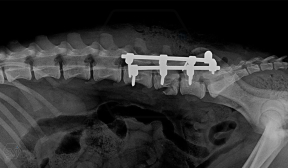

In our case, we created a shoulder arthrodesis on an 11-year-old 16kg female beagle dog with a 2.7 SOP-LC system and 4-4 clamps. The dog developed chronic arthritis and arthrosis, the biopsy did not confirm a tumor, only chronic inflammation.

There is no weak point in bridging the joint, which is inevitable in a plate bridging. Another great advantage is that the clamps can be placed according to anatomical needs, on either side of the rod and the screws can be inserted in any direction. Maximum stability is provided by the locking clamps, which is especially advantageous in a thin bone (scapula) or a bone with a porotic or thinned cortex (leg that has been used less for a long time). We have used the system several times in reoperations due to a broken plate.